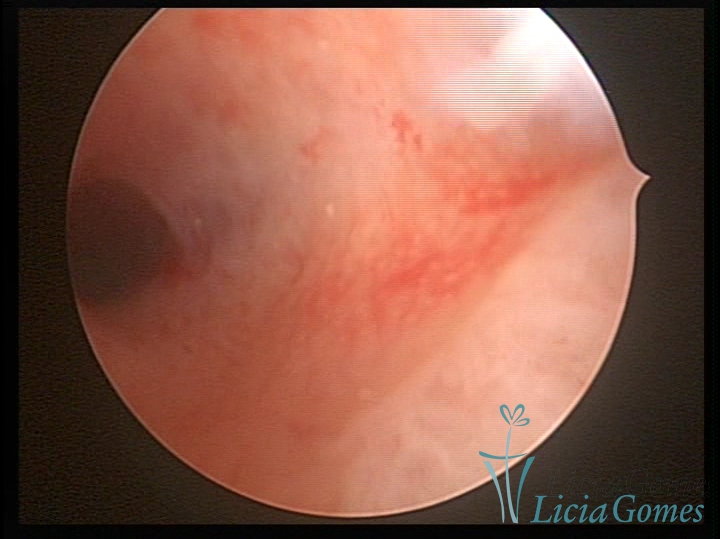

Septate uterus

It probably occurs by the lack of resorption on the middle line, in the merge of Müllerian ducts. The uterus is divided by a partial or total septum which is viewed as a crossbar, not covered by endometrium, which not bleeds when sectioned.

Complete septum when it occupies the whole extension of the cavity, dividing it into two hemicavities.

When this septum occupies only a part of the extension of the uterine cavity, it is considered as incomplete.